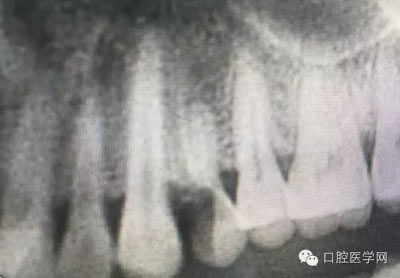

幾例根管再治療病例

根管再治療是我們比較頭疼的,尤其是那些冠修復過的,我們有很多的麻煩需要去溝通,比如可能導致的側(cè)穿、可能沒有看到的腐質(zhì)、可能導致的崩瓷,或者是后期可能出現(xiàn)冠折......這些需要我們和患者好好的溝通。全瓷冠還好些,金屬冠根測的時候很是麻煩,總之我們做修復的時候不要單純的追求速度,追求效益,適當?shù)淖⒁庀挛覀兊幕A(chǔ)治療和設(shè)計。